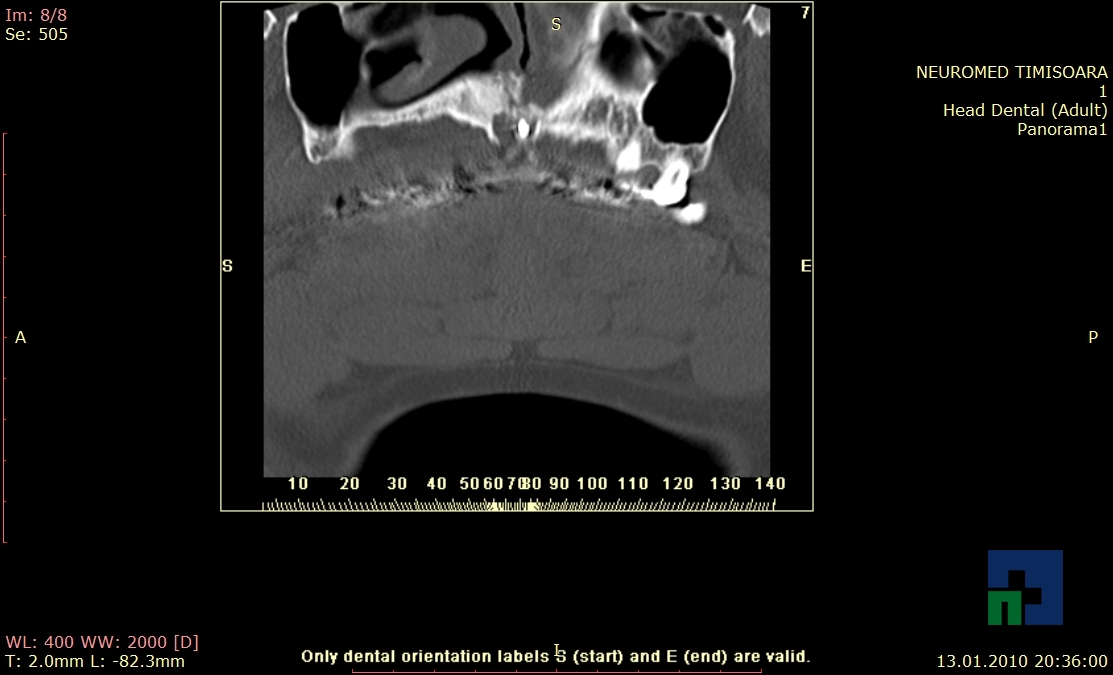

- Diagnosticul traumatismelor de bază de craniu

- Diagnosticul fistulei LCR